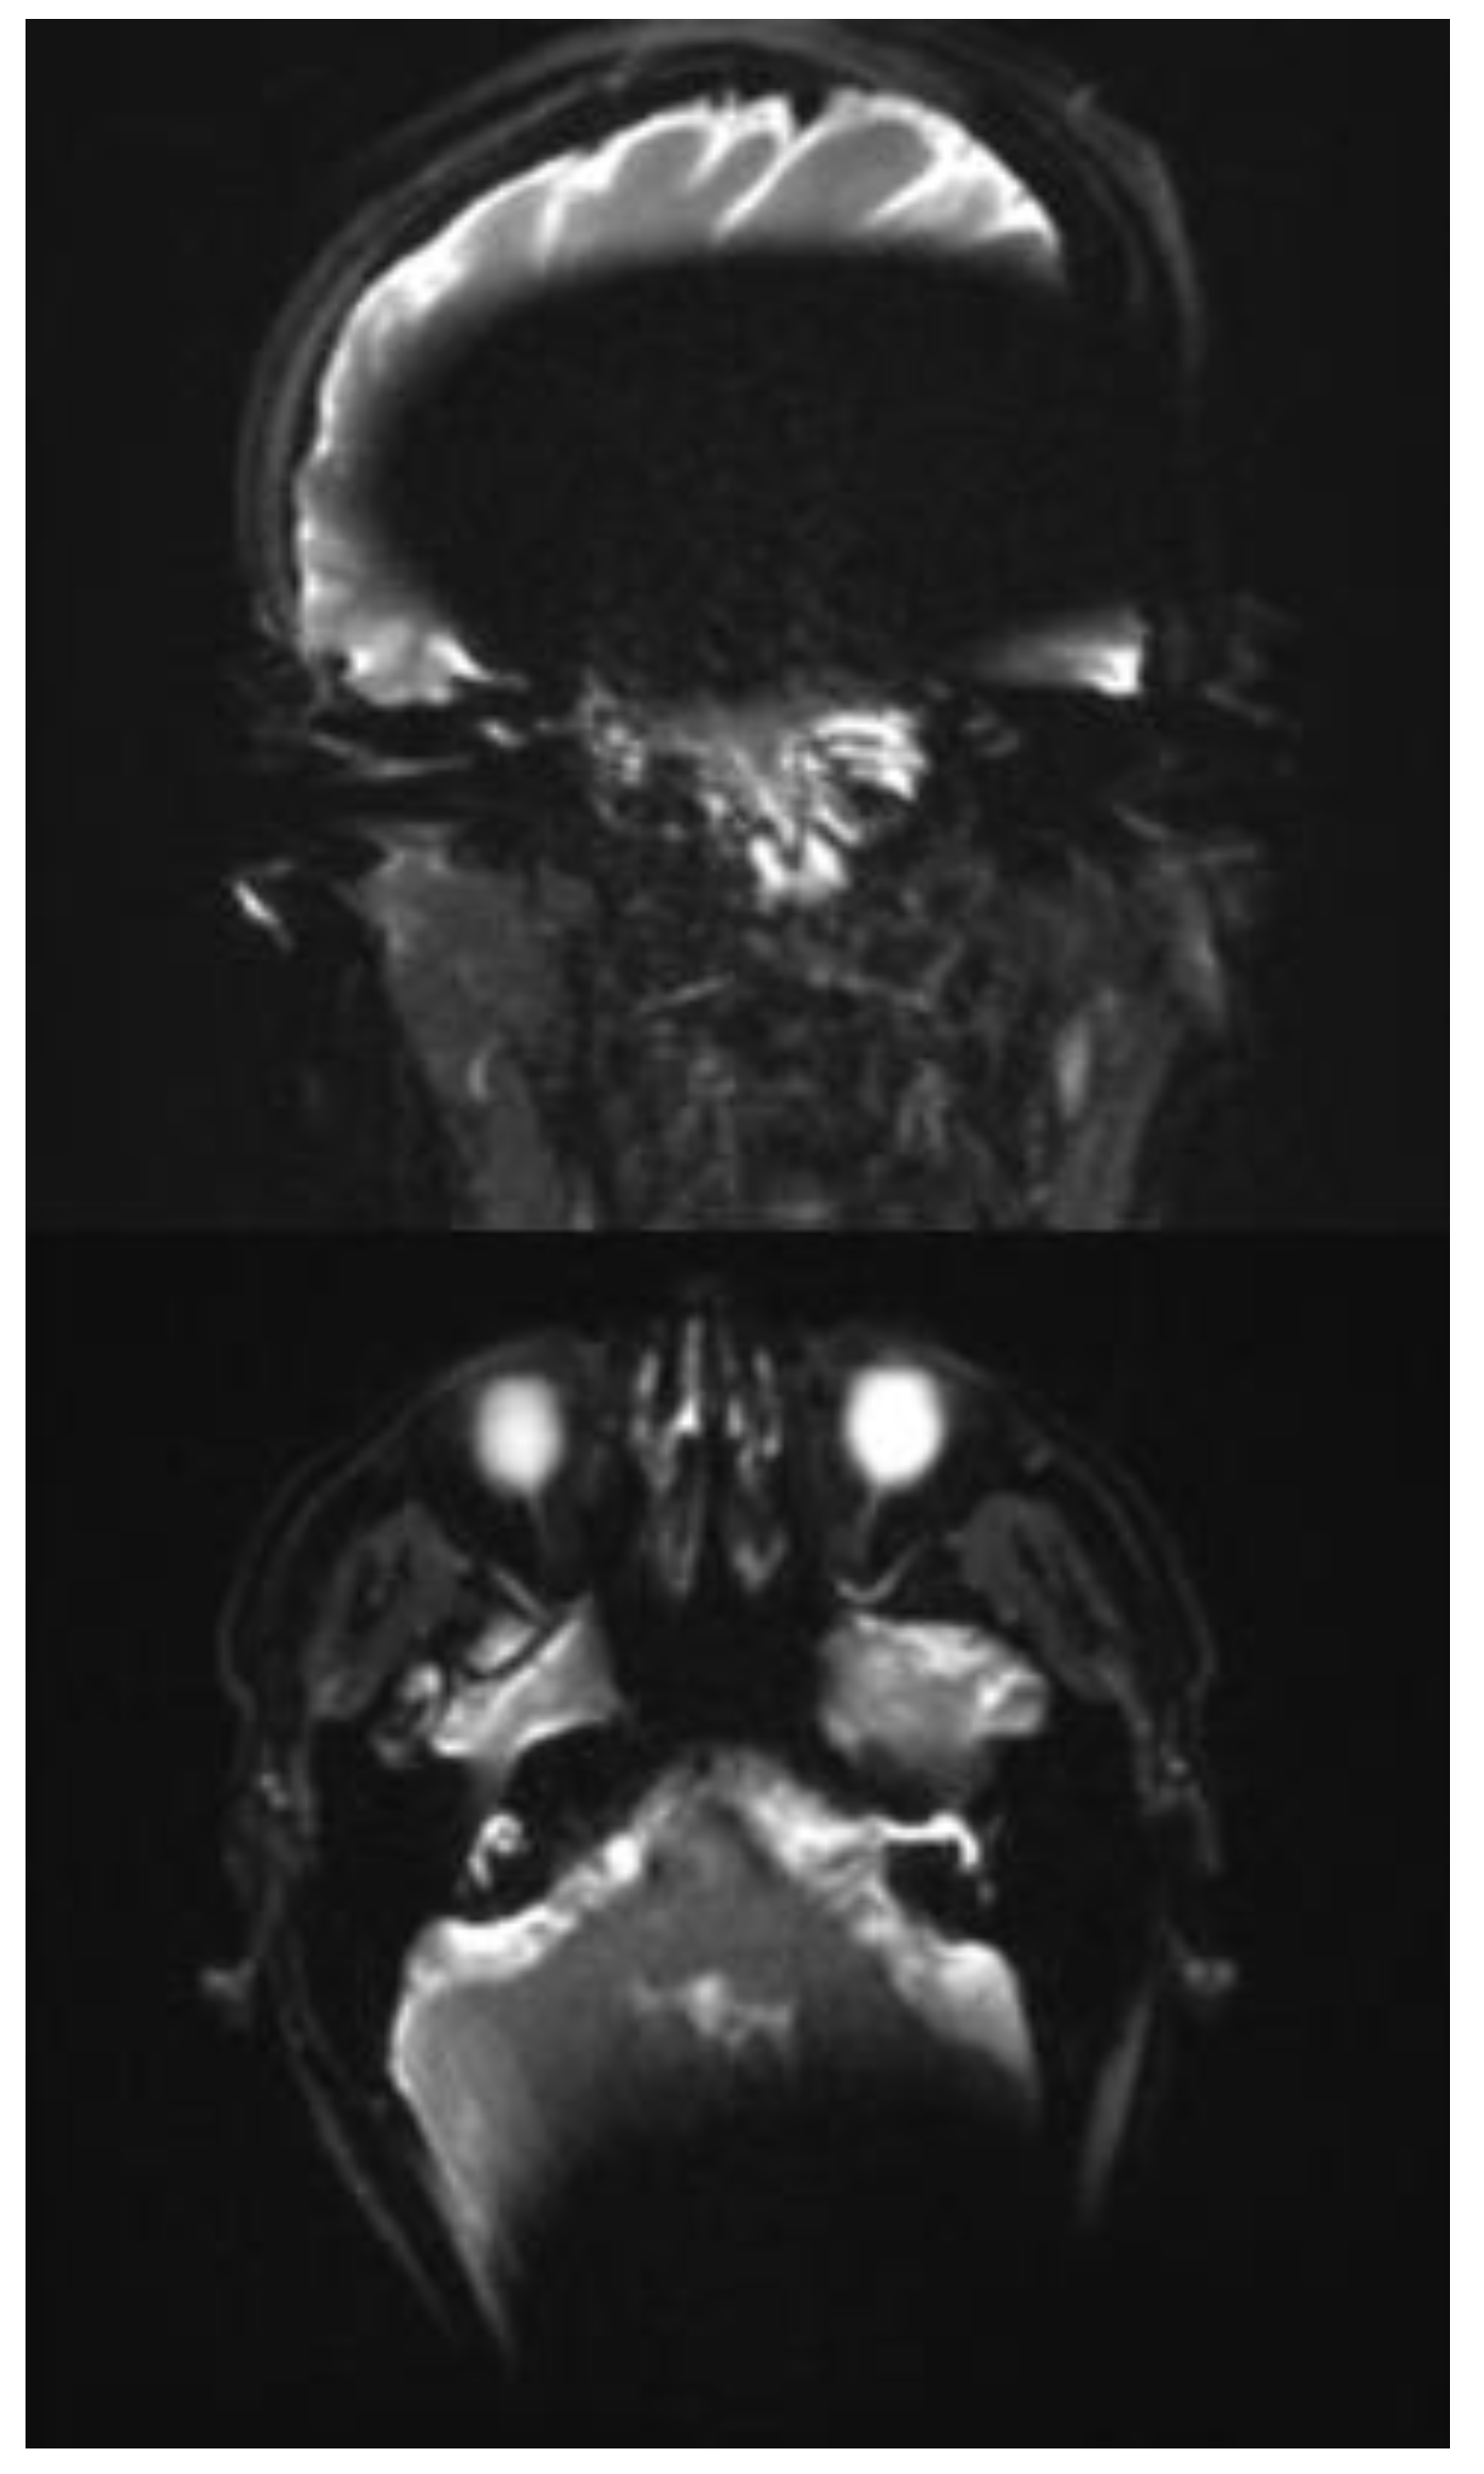

In all three subjects, the EP2D diffusion sequence shows a pronounced susceptibility artifact in both the axial and coronal planes with areal signal loss and, in some cases, considerable geometric distortions. Around the cochlear implant, central, hypointense signal losses with hyperintense fringes are impressive, whereby these fringe phenomena appear particularly pronounced in the coronal plane.

Due to the pronounced stretching and distortion effects, anatomically correct visualization of the mastoid cavities, the external auditory canal, and the internal auditory canal is considerably impaired on both sides. (Figure 2a,b).

Figure 2. a and b Exemplaric scan with an EPI2D sequence 3 T in a coronal and axial plane.

In the transverse as well as in the coronal image plane, a localized signal loss in the region of the cochlear implant can be seen, corresponding to a pronounced metal-induced susceptibility artifact. The average artifact extension in the axial orientation is 108 mm (subject 1: 103 mm; subject 2: 106 mm; subject 3: 116 mm), while in the coronal plane, it is 146 mm (subject 1: 156 mm; subject 2: 147 mm; subject 3: 134 mm). In the coronal image, a disproportionate craniocaudal and mediolateral artifact extension is also impressive, which extends beyond the temporal lobe to the midline and projects into deeper contralateral brain sections.

In each case, the artifacts are accompanied by geometric distortions as well as grid- or band-like signal inhomogeneities in the peripheral area.

In all three cases examined, the ipsilateral mastoid air cell can be visualized mainly in both planes. In subjects 2 and 3, however, the distal section of the ipsilateral mastoid exhibits a partial artifact overlay, which limits assessment. The contralateral mastoid cavity can be assessed in its full extent in all subjects without restrictions.

In the axial plane, both the ipsilateral cochlea and the internal auditory canal remain unaffected by the artifact spread. The course of the internal auditory canal can be visualized artifact-free up to the cerebellopontine angle and assessed without any discernible geometric distortions. In the coronal view, however, complete traceability of these structures is not reliably possible due to superimposed artifacts. The same applies to the visualization of the external auditory canal, which can only be assessed to a limited extent in the coronal plane due to artifacts. (Figure 3a and b).

Figure 3. a and b. Exemplaric scan with a RESOLVE sequence 3 T in a coronal and axial plane.